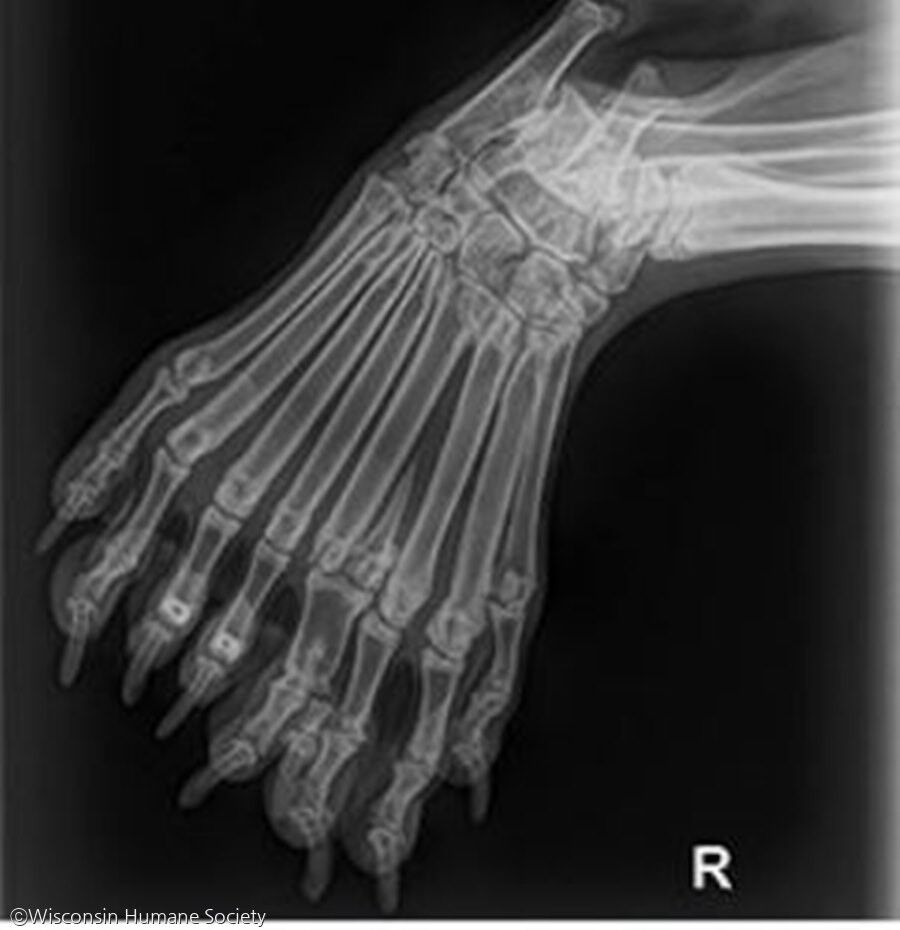

강아지의 이름은 '벨라(Bella)'로, 녀석은 다른 강아지들과 조금 다르다. 오른쪽 뒷다리가 1개가 아니라 2개이며, 발가락을 9개나 갖고 있다.

보호소가 지난 26일 페이스북에 공개한 사진은 벨라의 몸과 발을 담았다. 엑스레이 사진을 보면, 9개의 발가락뼈와 2개의 뒷다리 뼈를 확인할 수 있다.